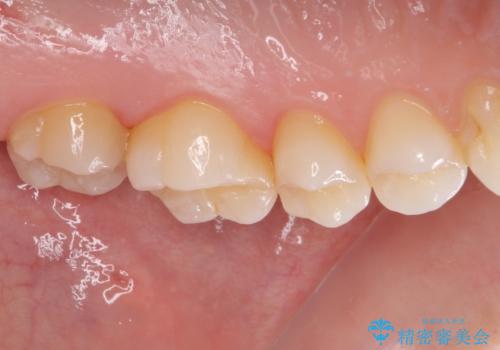

ゴールドインレーは銀歯のインレーやセラミックインレーと比べ、「技工操作の精度が高く、適合が著しく良い」というメリットがあります。特に上の奥歯は歯科医師の操作が行いにくいため、「適合の良さ」は再治療のリスクを防ぐ上でとても重要な要素となります。

上の奥歯は金属色が見えることもないため、審美的な問題は全くありません。

咬み心地はとても良好で、全く違和感がなく、患者様には大変満足していただきました。